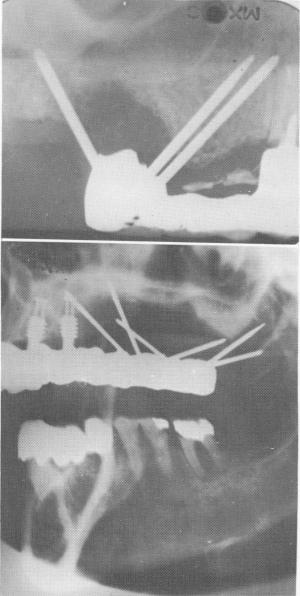

Fig. 14-30. When other teeth as well as other post type implants are used as abutments for the support of a full arch fixed denture, the longevity of triplants used without a template is increased. However, success is more assured with a template.

Fig. 14-32. The triplants in these two cases are failing as a result of excessively thick fibromucosal tissue that restricted the depth of the pins into the bone.